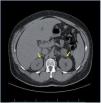

Dentro del estudio de HTA secundaria, el perfil tiroideo fue normal, así como las catecolaminas en orina. El paciente no refería ninguna sintomatología que orientase a causa de HTA secundaria, salvo una leve astenia y ser roncador crónico. Por ello se realizó un estudio de polisomnografía, con el diagnóstico de síndrome de apnea-hipopnea grave durante el sueño de predominio de apneas centrales, instaurándose tratamiento con CPAP (presión positiva continua en la vía respiratoria) nocturna. El paciente presentaba un mal control tensional, a pesar de la asociación de 4 fármacos a dosis plenas (torasemida, amlodipino, doxazosina y enalapril) y persistía con valores de potasio en torno a 3,5 mEq/l, pese a suplementos de potasio y dosis máxima de enalapril. Ante la sospecha diagnóstica de HTAM secundaria a HAP, se solicitó una TC abdominal, que mostró un engrosamiento difuso de ambas glándulas suprarrenales sugestivo de hiperplasia (fig. 3). A pesar de estar recibiendo el tratamiento hipotensor previo, se realizaron valores de renina y aldosterona plasmática, y se obtuvieron unos valores de 3 pg/ml y 320 pg/ml, respectivamente. En pacientes con una relación de aldosterona/ renina plasmática mayor de 50 y valores elevados de aldosterona, el diagnóstico de HAP es casi siempre confirmado, independientemente del límite inferior de la renina plasmática. Aunque no se debe olvidar que los valores de corte son diferentes según la medición de la concentración de la renina plasmática30.

Figura 3. Tomografía computarizada suprarrenal del caso clínico 2. Las flechas amarillas señalan el engrosamiento difuso de ambas glándulas suprarrenales.